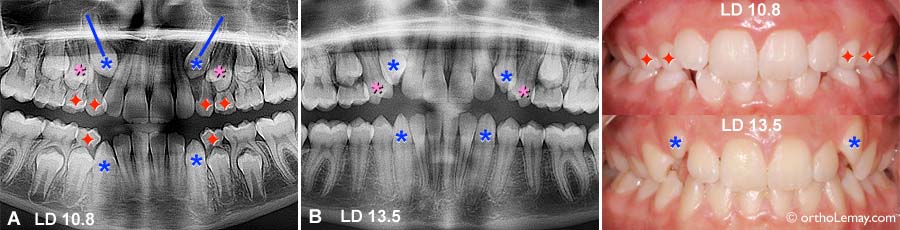

Cas LD

Cas LD : (A) À 10.8 ans, les canines et premières prémolaires supérieures sont inclinées vers l’avant. Les canines sont en contact avec les racines des latérales. (B) Près de 3 ans plus tard, après avoir fait des extractions sélectives , les canines se sont redressées et sortent dans une bien meilleure position. La situation s’est aussi améliorée à l’arcade inférieure. (Voir la légende pour identifier les dents)